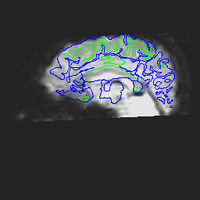

EPI images are significantly distorted relative to true brain anatomy. This is a problem because activation maps created from EPI images are overlaid on T1 images (or cortical surface models created from T1 images) which reflect the true anatomy. The following images show a T1 image with outlines for the outer boundary of gray matter (blue line) and white matter (green line).